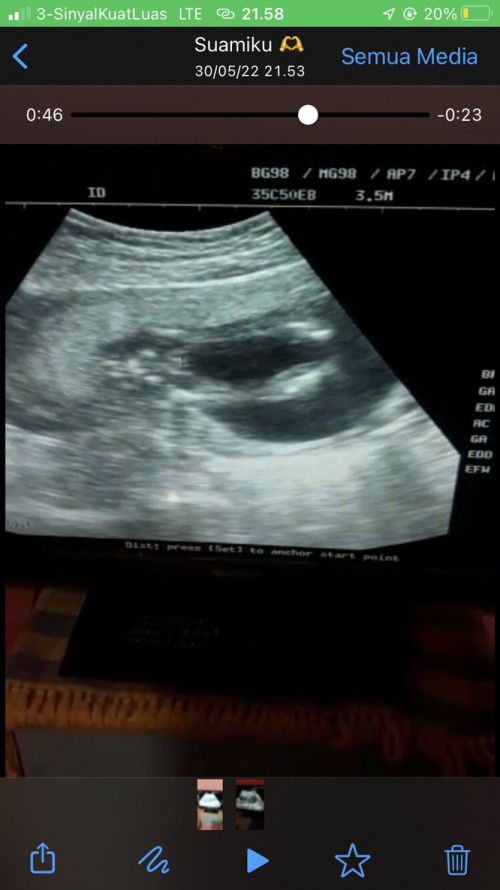

Ada yang tau jenis kelamin ini ?

Bunda ada yg bisa baca hasil usg tidak ? Aku sempet ragu karena usg di minggu 16 week kemaren dok bilang kemungkinan laki2 , tapi pas di cek usg kembali di minggu 20 katanya perempuan, jadi ini lebih memungkin kan ke laki laki apa perempuan ya ? #ingintahu #seriustanya #firstmom #firstbaby #pleasehelp